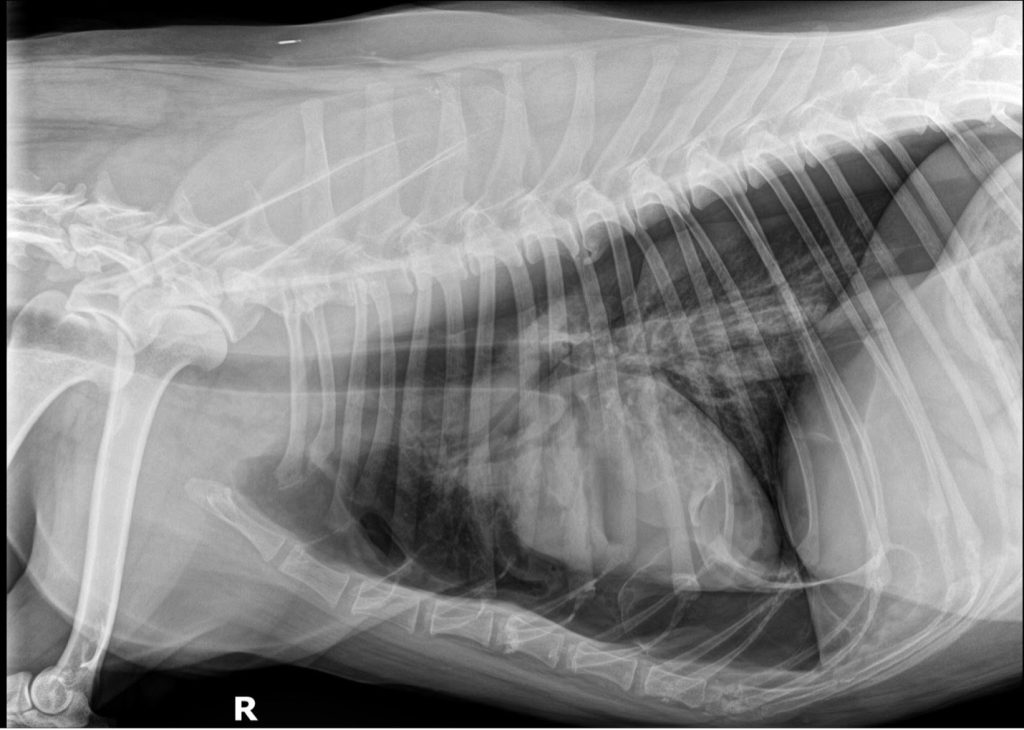

Approximately 1600 mL of air was aspirated by thoracocentesis. Serial radiographs confirmed significant improvement in free air volume, and the patient’s condition stabilized.

- Large-volume, bilateral pneumothorax

- Pulmonary alveolar pattern secondary to atelectasis

- No obvious lymphadenopathy

Radiographs have high sensitivity for diagnosing pneumothorax; however, they are significantly less sensitive and specific than CT in detecting underlying cause and/or extent of disease. Primary spontaneous pneumothorax is generally caused by one or multiple pulmonary blebs or bullae. CT has been shown to identify bullae up to 2.5 times more often than radiographs, which provides useful information regarding prognosis and surgical planning. CT can still miss 40–50% of bullae, however, and maintaining negative thoracic pressure with indwelling thoracostomy tubes can improve lesion identification.